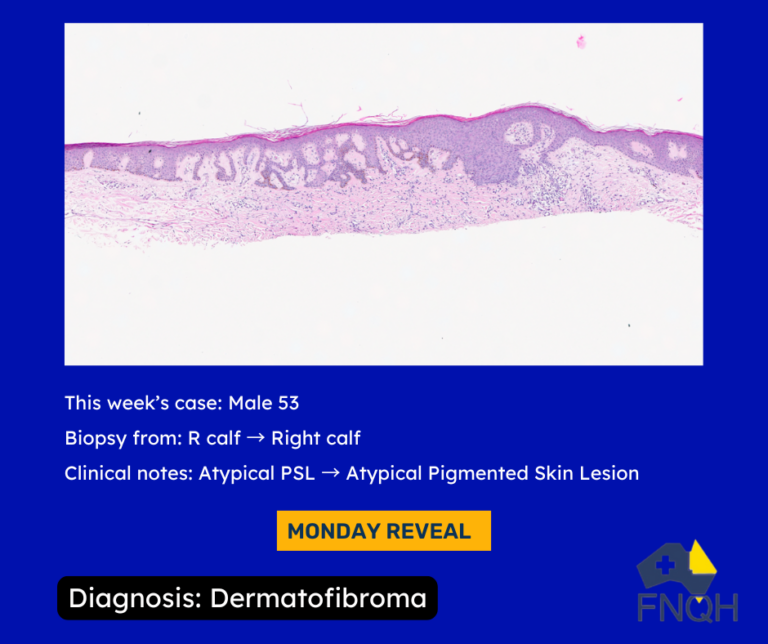

- 53-year-old male

- Biopsy from the right calf for assessment of an atypical pigmented skin lesion.

- Dermatofibroma